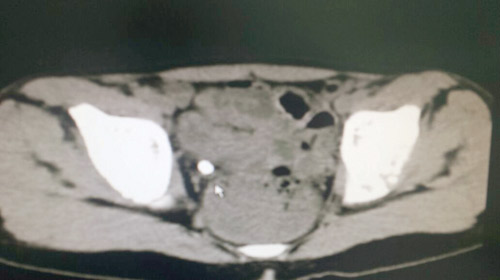

تمكَّن الفريق الطبي لقسم جراحة المسالك البولية بالمستشفى السعودي الألماني بالرياض من استخراج حصوة كبيرة من الحالب الأيمن لطفل، يبلغ من العمر ست سنوات، وذلك باستخدام المنظار والليزر بدون جراحة. وكان الطفل صاحب السنوات الست يعاني نوبات عديدة ومتكررة وشديدة من مغص كلوي حاد في الجانب الأيمن مع بول مدمم. وبإجراء الفحوصات الطبية اللازمة تبيَّن وجود حصوة كبيرة في الحالب الأيمن؛ فتم إجراء عملية تفتيت للحصا بالليزر واستخراجها عن طريق المنظار بدون جراحة في قسم جراحة المسالك البولية. وقد خرج الطفل -بحمد الله تعالى- من مستشفى السعودي الألماني بالرياض بعد يوم واحد من إجراء العملية بحالة صحية ممتازة، وينعم بالصحة والعافية بفضل الله تعالى وتوفيقه. من الجدير بالذكر أن نسبة الإصابة بحصوات المسالك البولية قد ارتفعت خلال العقدين الماضين. ومن أهم وسائل الوقاية من الحصوات في المسالك البولية هي المحافظة على شرب السوائل بنسبة كبيرة ومنتظمة، بما لا يقل عن لترين في اليوم، وكذلك التقليل من اللحوم الحمراء والأملاح، وخصوصًا الوجبات السريعة.